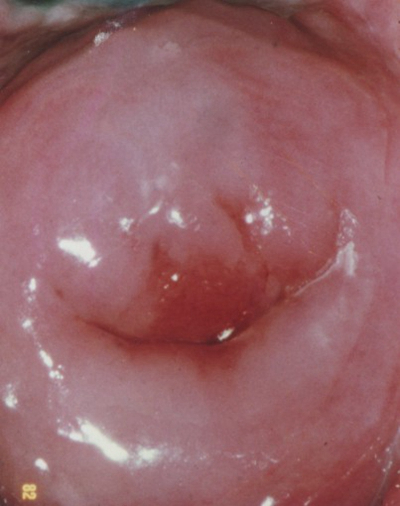

淋病圖片

淋病的症狀 (7)

淋病的症狀 (8)

淋病的症狀 (9)

淋病的症狀 (47)

淋病的症狀 (48)

淋病的症狀 (49)

淋病的症狀 (5)

淋病的症狀 (50)

淋病的症狀 (51)

淋病的症狀 (52)

淋病的症狀 (53)

淋病的症狀 (54)

淋病的症狀 (55)

淋病的症狀 (56)

淋病的症狀 (6)

淋病的症狀 (40)

淋病的症狀 (41)

淋病的症狀 (42)

淋病的症狀 (43)

淋病的症狀 (44)